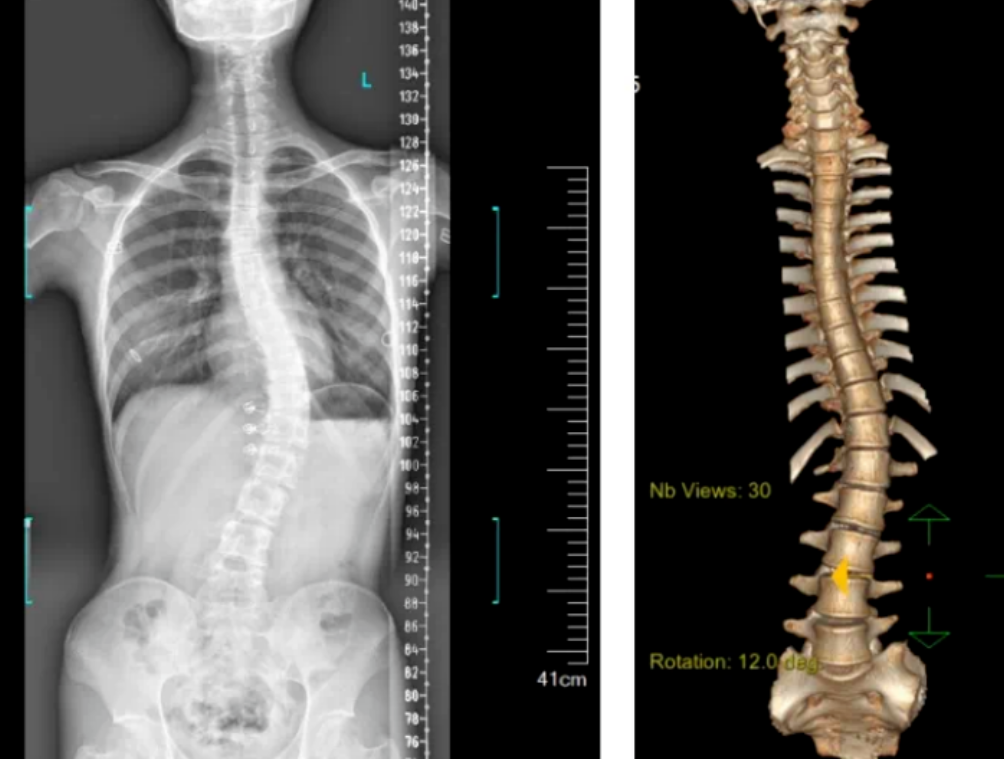

3D機器視覺的脊柱檢測圖

3D視覺技術(shù)可以用于自動化的脊柱側(cè)彎檢測。通過使用3D成像設(shè)備,如結(jié)構(gòu)光或激光掃描儀,機器人可以快速捕捉老年人的脊柱圖像,并利用機器視覺算法分析脊柱的形態(tài)和角度,從而判斷是否存在側(cè)彎現(xiàn)象。

基于顯揚科技HY-HY-X3 3D機器視覺的脊柱側(cè)彎檢測系統(tǒng),能夠在無需接觸患者的情況下,快速獲取患者脊柱的三維圖像。該系統(tǒng)使用高精度的3D攝像頭,通過結(jié)構(gòu)光或激光掃描技術(shù),捕捉到脊柱的詳細(xì)形態(tài)。

系統(tǒng)掃描速度為15Hz,精度達(dá)到±0.01mm,結(jié)合自研智能算法,能夠進行全彩信息學(xué)習(xí),還能通過深度攝像頭捕捉人體背部的形態(tài)變化,轉(zhuǎn)化為對應(yīng)的脊柱形態(tài),并計算脊柱的彎曲角度,從而了解患者的側(cè)彎程度。這種方法避免了傳統(tǒng)X光片檢測帶來的輻射風(fēng)險,實現(xiàn)了無輻射、快速、便捷的篩查。